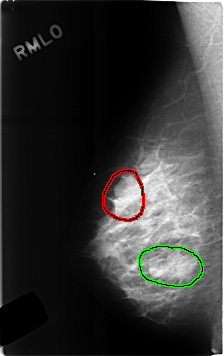

C_0306_1.RIGHT_MLO

FILE: C_0306_1.RIGHT_MLO.OVERLAY

TOTAL_ABNORMALITIES 2

ABNORMALITY 1

LESION_TYPE MASS SHAPE LOBULATED MARGINS OBSCURED

ASSESSMENT 4

SUBTLETY 5

PATHOLOGY BENIGN

TOTAL_OUTLINES 1

BOUNDARY

ABNORMALITY 2